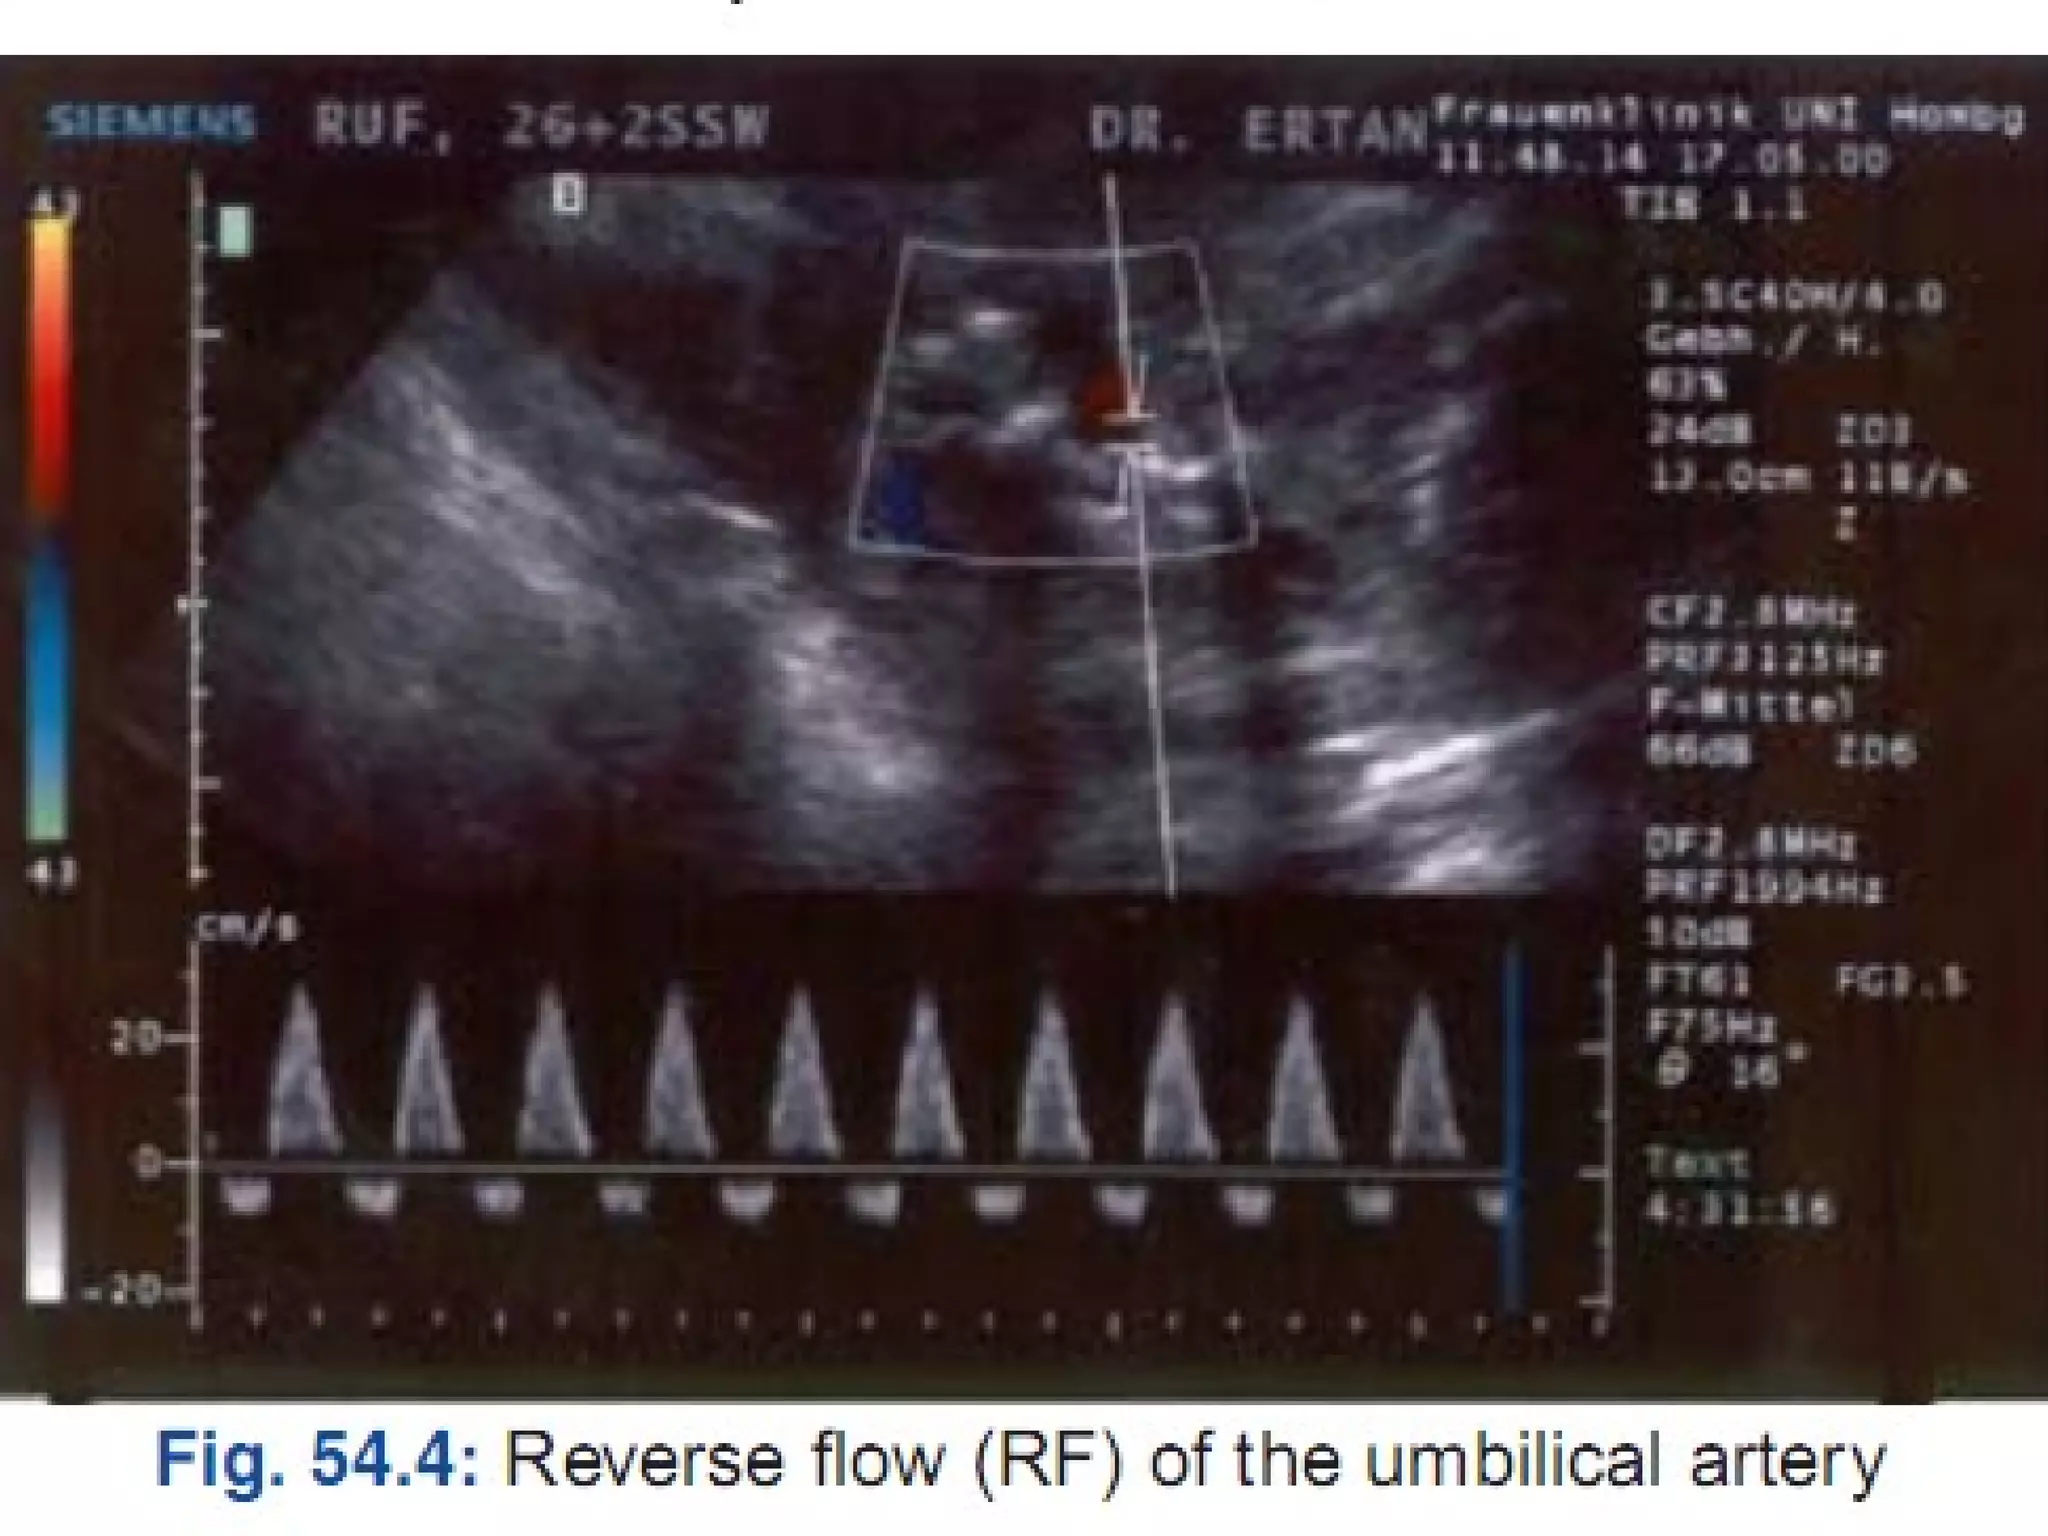

Umblical Artery doppler- In IUGR there is

increased umblical artery resistance (increased

S/D ratio), absent end diastolic flow and finally

reversed end diastolic flow.

Perinatal mortality rate increases significantly in

fetuses with absent end diastolic flow (9-41%)

and reversed end diastolic flow (33-73%) in

umblical artery.